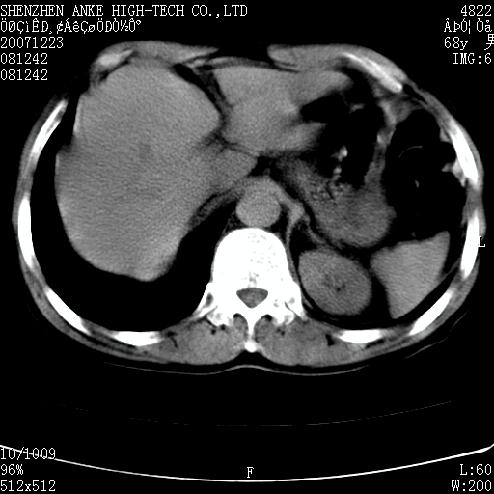

患者:男,63岁,2年前胆囊切除术后,现右上腹部剧烈疼痛近2天.

有无外伤史?右肾包膜下血肿可疑。

主要是问右肾有没有问题?患者无明显外伤史.

未见异常,病人差闭气,伪影较多.

上腹部ct平扫未见明显异常。

肠道准备不好,胃底后壁显示不清,右肾改变考虑为伪影。

请看第一张正位片,胸主动脉象有扩张,胸主动脉瘤?